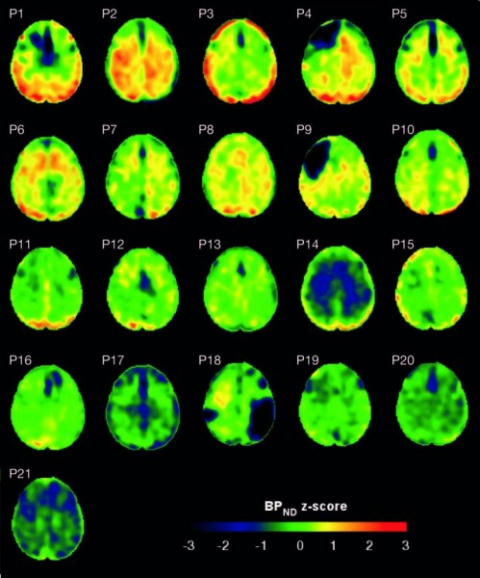

Cuarenta y seis pacientes con la enfermedad de Huntington y 35 controles sanos se sometieron a una evaluación psiquiátrica de la apatía en sus tres dominios, además de varias pruebas de imagen, para estudiar si las diferencias individuales en tractos cortico-estriatales específicos predecían la apatía global y sus subdominios.